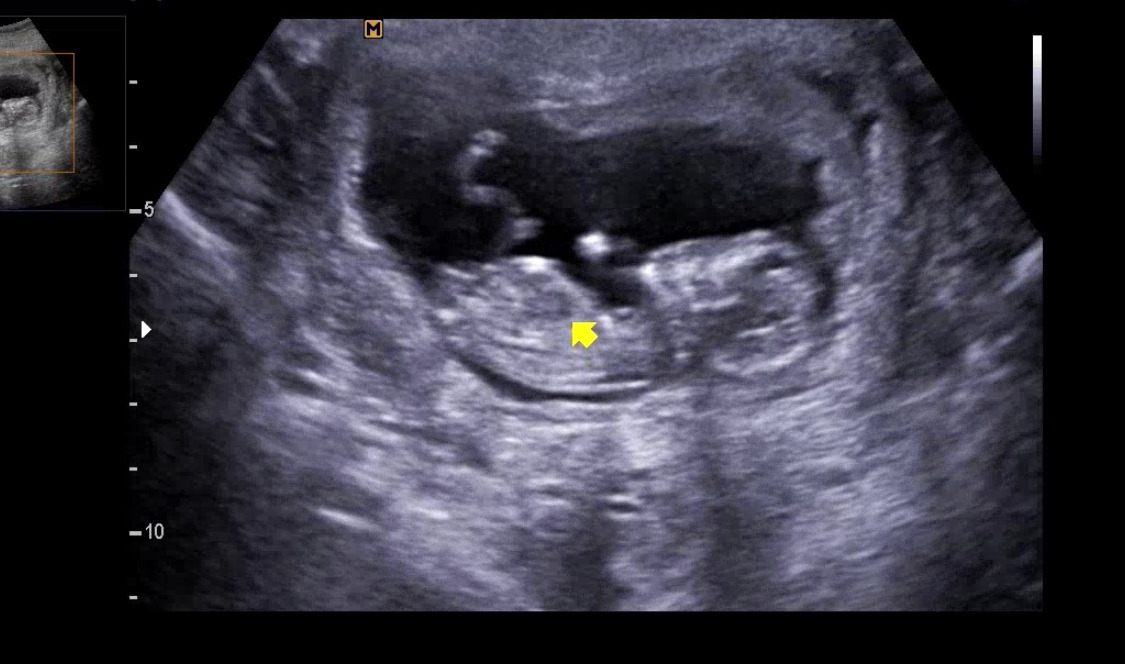

다운증후군의 마커로서 코뼈 유무와 NT(목덜미 투명대, 자세한 내용은 https://brunch.co.kr/@the-cosmos/17 '다운증후군 산전검사에 대하여') 두께를 확인했다. 코뼈도 정상적으로 잘 보였고, 아기의 NT 두께는 1.1mm로 정상범위였다. 이제는 태반에 연결된 탯줄도 제법 잘 보이고, 얼굴 윤곽도 조금 보이는 듯했다. 양손과 양 발, 뇌부터 방광까지 현재 확인할 수 있는 장기까지 잘 확인하고는 써니의 첫 4D 초음파를 촬영했다. 지금까지 잘 있다가 검사가 끝나니 꼬물거리는 아기. 얼굴을 보여주지 않으려고 돌아 눕다가, 잠깐 정면을 보여줬다. 안녕 써니야!

KakaoTalk_20220629_170123889_01.jpg 인생 첫 사진, 반가워 써니야!